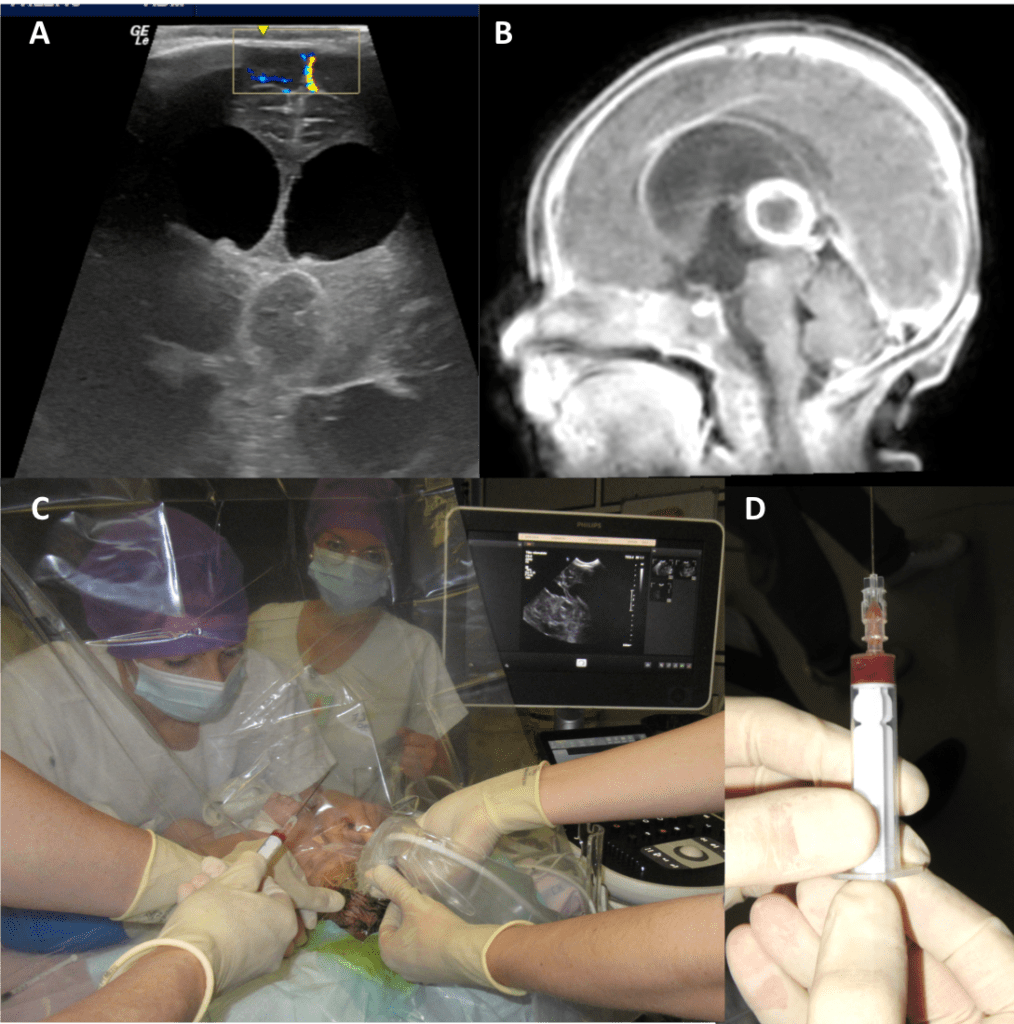

elle consiste au minimum en une ponction de l’abcès, par trépanation, éventuellement guidée par neuronavigation, ou par ponction trans-fontanellaire éventuellement sous contrôle échographique. il s’agit le plus souvent d’une urgence chirurgicale en raison du risque d’aggravation rapide au plan neurologique comme au plan infectieux.

on peut réaliser une ponction percutanée au lit du patient en réanimation (Cf. ci-dessus), qui peut être utilement guidée par l’échographie (Cf. ci-dessous)